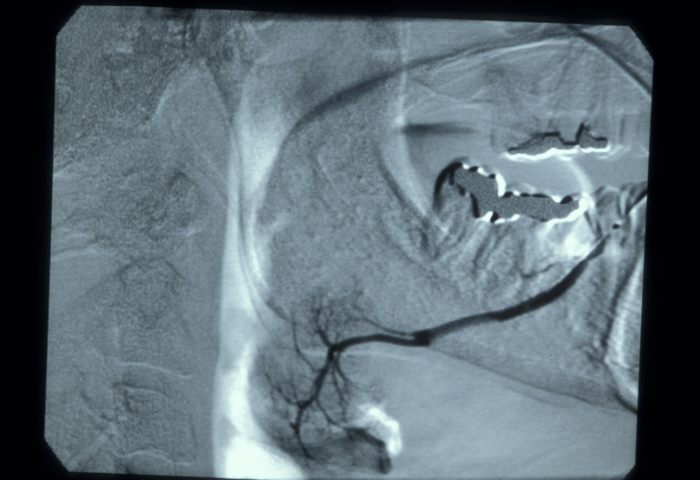

In the duct, a calculus is date shaped, at the junction of duct and gland it is comma shaped and in the gland it is round. Should a calculus not be visible on plain X-ray images, a sialogram is required which may demonstrate a radiolucent stone, a mucus plug or a stricture in the duct (see Figure 3).

Figure 3: A siaologram. These images are useful diagnostically and therapeutically.

In those cases with a history of parotid swelling a sialogram will show a characteristic ‘snowstorm’ appearance of punctate sialectasis (spots of dilation of ducts) in Sjögren’s syndrome (see Figure 7). Decreased tear secretion can be measured objectively using small strips of paper placed in the lower eyelid (Schirmer’s test).

Figure 7: Sialogram showing mild ‘snowstorm’ appearance typical of sialectasis in Sjögren’s syndrome.